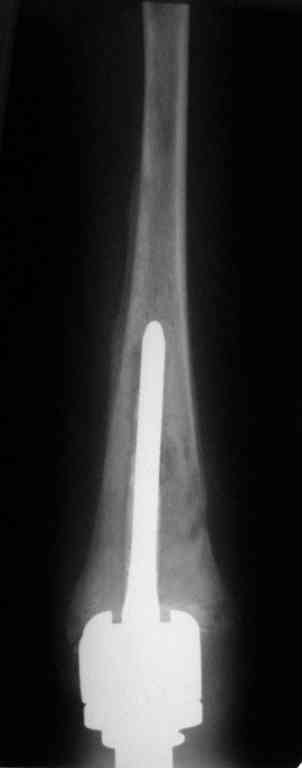

Уважаемые коллеги! Хотелось бы узнать ваше мнение о тактике лечения пациентки 16 лет, диагноз - б-нь Гоше I типа, состояние после резекции проксимальных 2/3 левой большеберцовой кости, тотального эндопротезирования ЛКС онкологическим эндопротезом, перипротезная инфекция.

01/08/05

09/09/05

13/01/06

Протез установлен год назад, в течение 8 месяцевфункционируют свищи, сообщающиеся с компонентами эндопротеза.

Планируется оперативное лечение, которое ранее не выполнялось по причине низких показателей крови (Тц-30, Нв-50, Лц-2,5) после химиотерапии. В настоящее время показатели крови постепенно нормализуются и встаёт вопрос о тактике хирургического лечения.

Пациентку беспокоят боли в нижней трети голени при физической нагрузки.